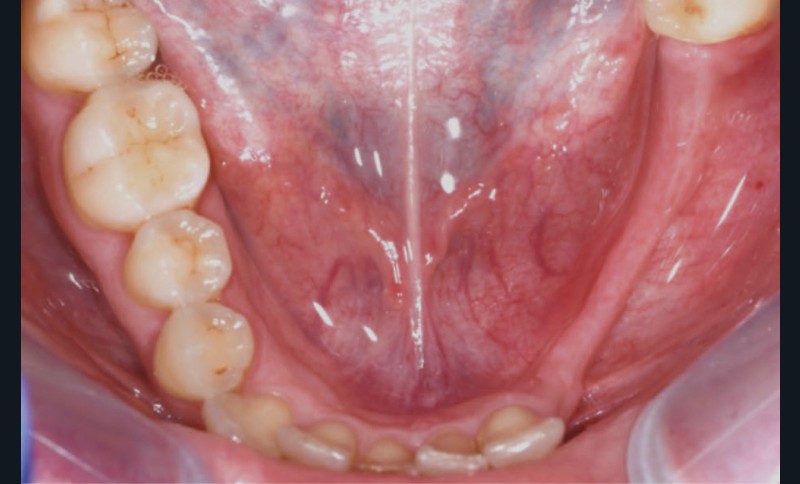

L’examen facial est sans particularités notables. L’examen buccal retrouve un édentement de 33 à 36, compensé par une prothèse amovible, avec une atrophie osseuse transversale et verticale majeure entraînant une augmentation de l’espace prothétique. Il persiste un fin bandeau de gencive kératinisée crestal. Le reste de la denture est sain, l’articulé est en classe I avec un inversé d’articulé sur 13 (fig. 1).